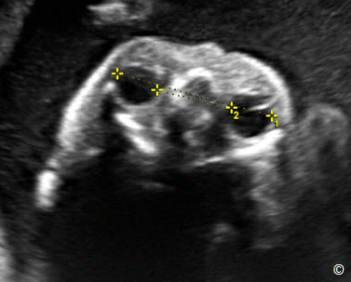

Figure 5.2: Transverse plane of the fetal head at the level of the biparietal diameter (BPD) showing

correct caliper placement. Note that the upper and lower calipers are traditionally placed on the

outer and inner edge(s) of the cranium respectively (GA = gestational age and EFW = estimated fetal

weight).

Hình 5.2: Mặt cắt ngang lưỡng đỉnh cho thấy vị trí đúng khi đặt con trỏ để đo. Chú ý điểm trên và dưới

của điểm đo là bờ ngoài bản sọ gần và bờ trong của bản sọ xa. (GA = gestational age- tuổi thai và EFW

= estimated fetal weight- ước lượng cân nặng).

Table 5.

Procedure for the Measurement of the Biparietal Diameter (BPD).

See Figure 5.2

- Activate the biometry software (calculate knob) on the console of the ultrasound

equipment

- Select the BPD option, a caliper will appear on the monitor

- Position the caliper on the outer edge of the proximal parietal bone, roughly at the

level of the thalami, where the head is wider, and set it

- Position the second caliper, symmetrically, on the inner edge of the distal parietal

bone, in such a way that the line between the two calipers is at 90° with the

midline falx, and set it.

- Ensure that the BPD measurement is the widest possible and is perpendicular to

the midline falx.

Tiến trình đo đường kính lưỡng đỉnh (BPD)

Xem hình 5.2

- Vào mục đo các chỉ số sinh học (ấn vào nút đo trên bàn phím) trên máy siêu âm.

- Chọn BPD, thang đo sẽ xuất hiện trên màn hình.

- Vị trí của thanh đo thứ 1 đặt ở bờ ngoài bản sọ đính gần, ngang mức đồi thị.

- Đặt con trỏ thanh đo thứ 2 ở bờ trong bản sọ xa, chú ý đường nối 2 điểm đó vuông

góc với đường giữa liềm não.

- Đảm bảo sao cho đường kính lưỡng đỉnh là lớn nhất và vuông góc với đường giữa

liềm não.